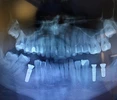

Periimplantitis

Ağız diş ve çene cerrahisi